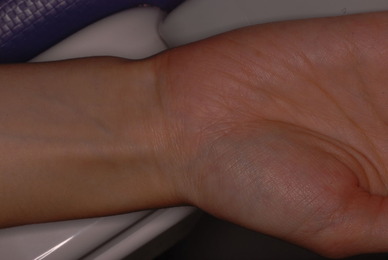

²¼³Ü²£¸þ¤¤Î¿ÆÉÔÃΤòºòÆüÈ´»õ¤·¤¿Êý¤ÎËÜÆü¤Î¾õÂ֤Ǥ¹¡£

°ì±þÌô¡Ê¾Ã±êÄÃÄ˺ޡˤò½Ð¤·¤Æ¤¤¤Þ¤·¤¿¤¬¡¢°ìγ¤â»ÈÍѤ·¤Æ¤¤¤Þ¤»¤ó¡£

Äˤߤâ¼ð¤ì¤â¤Ê¤¤¾õÂ֤Ǥ¹¡£Ë¥¤Ã¤Æ¤¤¤Ê¤¤¤Î¤ÇÈ´¤¤¤¿½ê¤ÏϪ½Ð¤·¤Æ¤¤¤Þ¤¹¡£¤À¤«¤é¤³¤½¼ð¤ì¤Ê¤¤¤Î¤Ç¤¹¤Í¡£Ë¥¹ç¤¹¤ë¤ÈÆâ½Ð·ì¤·¤Æ¼ð¤ì¤ë¤Î¤Ç¤¹¡£

»Äǰ¤Ê¤³¤È¤Ë½ý¸ý¤Ï³«¤¤¤Æ¤¤¤Þ¤·¤¿¡£